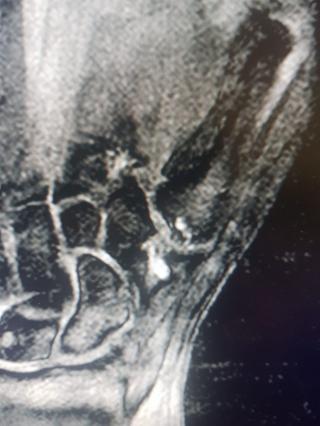

Мужчина 7 лет назад упал с мотоцикла. 4 и 5 палец практически не работают. Выраженный артроз мелких суставов кисти. После операции: движения в полном объеме. Болей нет.